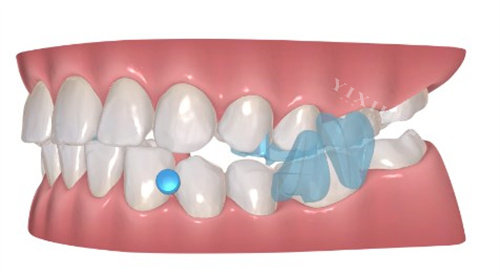

矫治特点

该产品采用日夜交替施力体系,日间版具有抗断裂性能好、回弹性强的特点,而夜间版则在补偿率优化和控制性方面表现突出。两种版本协同作用,形成复合矫治力,对于轻中度牙齿排列问题如不齐、拥挤等情况,能够提供持续的矫治力,有助于缩短整体矫治周期。

基于现代技术手段,该产品可为每位用户提供量身定制的矫治方案。通过正确测量和计算,确保矫治器与牙齿的贴合度,从而提高矫治过程的可控性和预期结果。